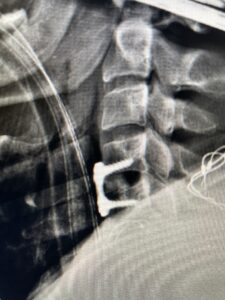

Fig 2a Sagittal and axial T2 weighted cervical MRIs demonstrating large C4 5 herniated disc with spinal cord compression red arrows

This 47-year-old male who four months prior was lifting weights developed sharp pain in his neck. After that he developed progressive numbness in his arms, neck pain and headache. He said that the right arm was worse than the left. On examination the patient had long tract weakness on the right side which included his triceps, finger extensors, hip flexors, and dorsiflexors. The patient did not have hyperreflexia. MRI (Fig. 2) demonstrated a massive, extruded disc herniation with severe cord compression. The patient because of progressive myelopathy and spinal cord compression was indicated for anterior cervical discectomy and fusion at C4-5 (Fig. 3). Patient had significant improvement of weakness and numbness post operatively.

Fig. 2a Sagittal T2-weighted cervical MRI demonstrating large C4-5 herniated disc with spinal cord compression (red arrow)

Fig: 2b Axial T2-weighted cervical MRI demonstrating spinal cord compression from C4-5 herniated disc (red arrow)